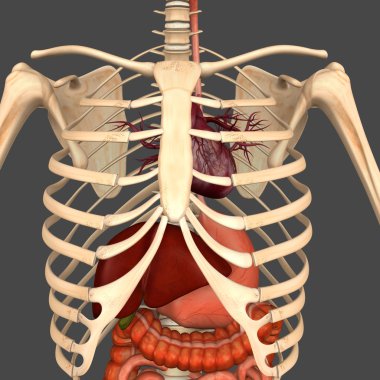

Sindirim Sistemi

En Çok Aranan Kelimeler

MaviresimlemeİnsanKadınSağlıkkanİlaçAğızSolunumerkekkalpgövdeMidebiyolojiBilimSistemözetorgİskeletanatomiKas gücübeyinSistemlersindirimGerginakciğerlerkaraciğerBöbrekiskeletOrganlaranatomikBağırsaklarBağırsakKolondolaşımdalakBenzer İçerikler